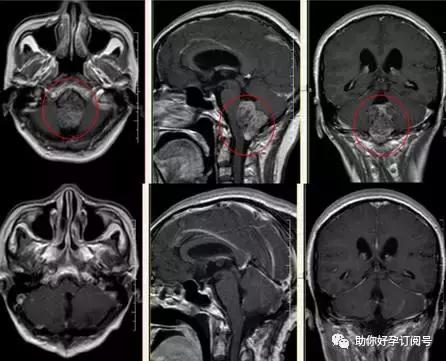

检查:颅内畸胎瘤影像学特征有其显著特点,可以作出初步诊断。

(4)MRI检查T1及T2像出现的信号极为混杂,但边界较清楚,呈结节状或分叶状,良性畸胎瘤边界无水肿(T2像显示清楚的高信号),如有周边水肿,提示肿瘤为恶变成分或恶性畸胎瘤,肿瘤在注药后瘤壁和实质部分明显强化。